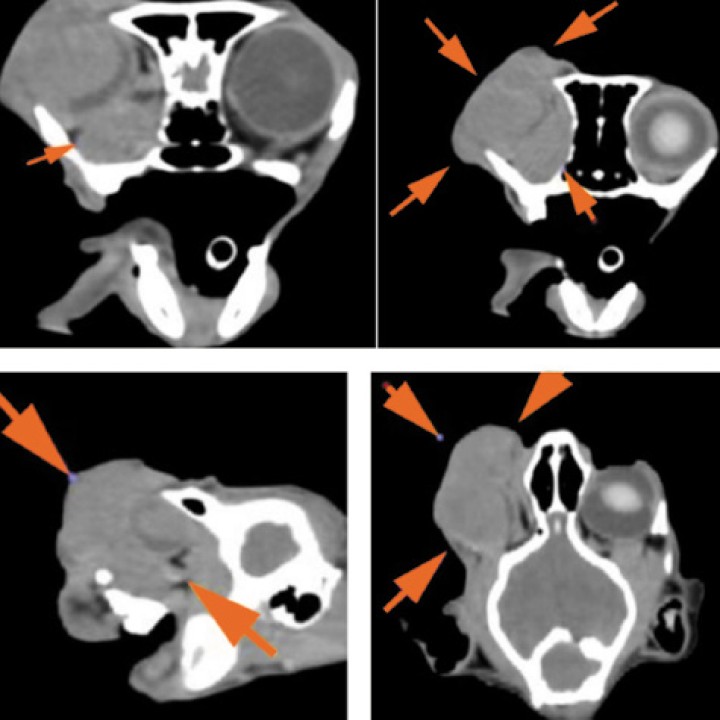

Finalmente, se realizó una tomografía computarizada (TC) de cabeza y tórax con el objetivo de identificar posibles metástasis regionales o a distancia, así como para facilitar una adecuada planificación quirúrgica. La TC no evidenció lesiones osteolíticas, linfadenopatías ni signos de diseminación metastásica, incluido el sistema nervioso central. Sin embargo, no fue posible descartar con certeza la invasión del nervio óptico, ya que la masa ocupaba por completo la cuenca orbitaria derecha, incluyendo el espacio retrobulbar y desplazando los vasos sanguíneos en dirección dorsocraneal. Esta extensión dificultó la evaluación precisa de la infiltración del nervio óptico y estructuras vasculares adyacentes. A pesar de ello, los hallazgos confirmaron la localización primaria de la masa en la región ocular derecha y la ausencia de diseminación a otros órganos en el momento del estudio (Figs. 3 y 4).

Figura 3

Imágenes tomográficas (transversal, sagital y coronal) donde se observa la masa de 3,3 × 3,7 × 5 cm (flechas) centrada en el globo ocular derecho, con atenuación de partes blandas y escasa captación periférica de contraste, que ocupa toda la órbita incluyendo el espacio retrobulbar, desplazando estructuras vasculares y con posible invasión del nervio óptico. Se extiende hacia el exterior sin provocar lesiones óseas en las estructuras adyacentes. Imagen cedida por el Hospital Bluecare.